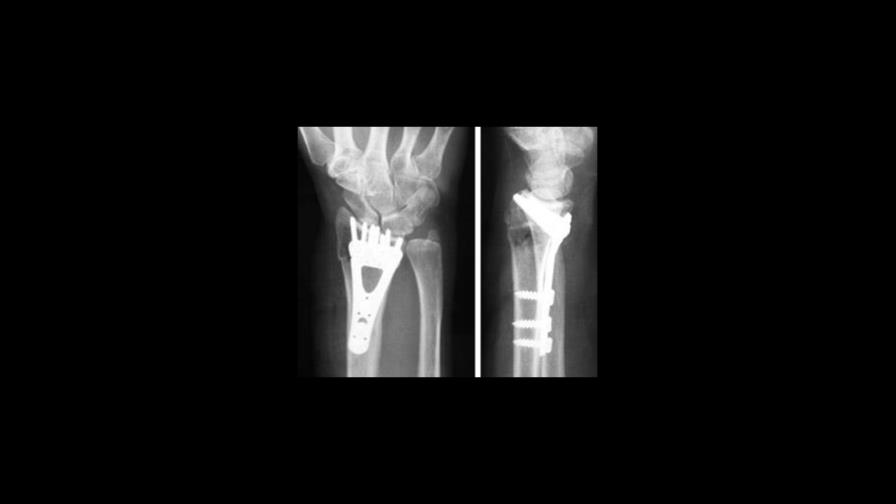

Catalán explicó que, “si en lugar de fabricar las prótesis de metal, se confeccionan de un material cerámico, y además a este material se le dota de la textura adecuada para que genere flexoelectricidad, podría ayudar a que la prótesis se implante bien, se calcifique bien”.

La comercialización de este tipo de prótesis aún está muy lejos, como aclaró Catalán: “la fase final del estudio no la podemos preparar en el ICN2, aquí únicamente desarrollamos un posible modelo, luego pasaremos la pelota a un hospital para que puedan hacer estudios clínicos con personas”.